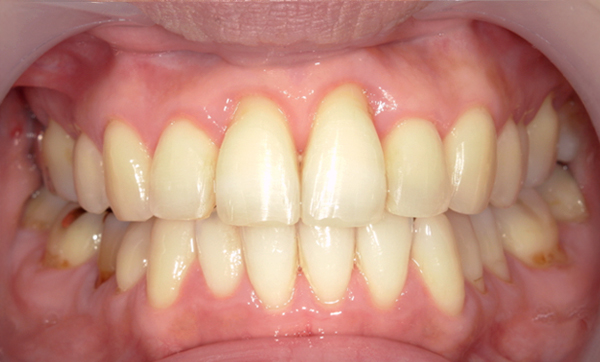

症例_002 上顎だけの部分矯正

治療期間:7ヶ月金額:30万円+税女性前歯のガタガタ上の前歯だけ

| Before | After |

|---|---|

|